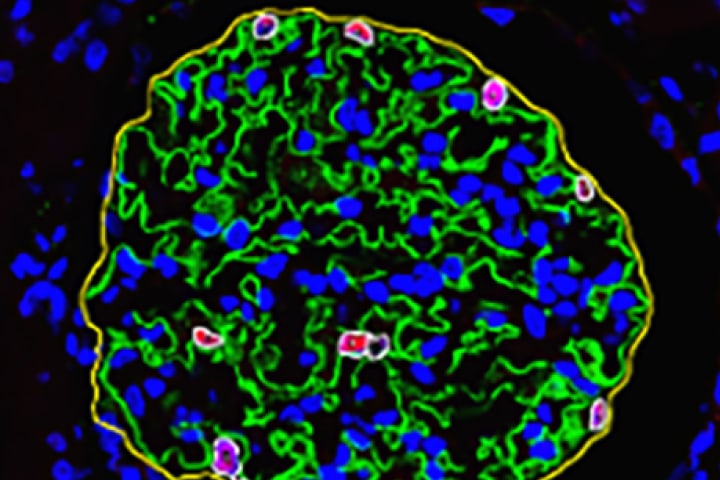

- Pathological specimen spatial analysis

- Pathology specimen analysis

・AI evaluation of kidney pathology images.